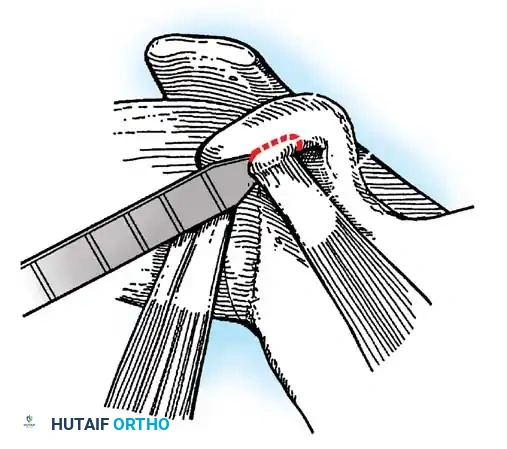

Capsulotomy and Joint Inspection

A vertical or T-shaped capsulotomy is performed based on the degree of capsular laxity and the planned shift.

- For a standard Bankart repair with an inferior capsular shift, a vertical incision is made 1 cm medial to the humeral articular margin. A horizontal limb can be added to create superior and inferior capsular flaps.

- Tagging sutures are placed in the capsular flaps for traction.

- A Fukuda retractor is placed within the joint to retract the humeral head laterally and posteriorly, exposing the anterior glenoid rim and labrum.